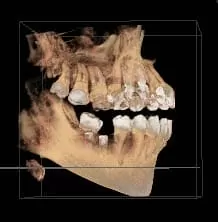

對於植牙醫師而言,CT的便利性,即是具有模擬植體植入的功能(圖2)。因為每位患者的顎骨結構不同,為了因應病人口腔現況及符合牙齒對應的咬合功能,植牙醫師需考量在術前判斷植體植入的位置是否恰當,由於CT所拍攝出來的影像是立體的,可以360度旋轉(圖3),可進一步判斷齒槽骨的骨質及植體植入的寬度與深度以避免植牙常見的問題案例:上排植體穿過鼻腔造成鼻竇破裂或是下排植體不小心碰到齒槽骨神經,可能造成半邊臉麻痺等問題發生(圖4)。所以進行拍攝「口腔電腦斷層CT」也是對患者進行植牙手術的安全與保障。

(圖3) 3D立體影像清楚呈現牙齒與口腔狀況